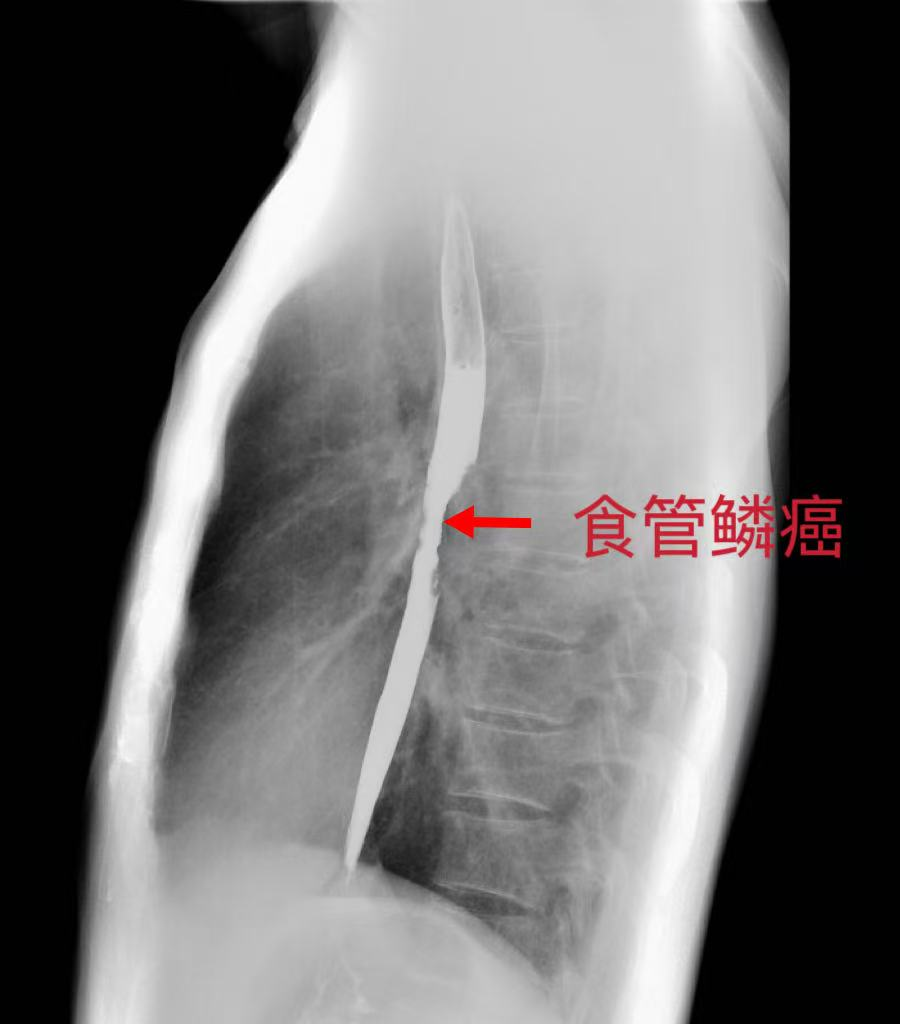

上消化造影提示:食管中段肿瘤

53岁的汤先生1个多月前出现进食梗阻症状,就诊于坪山区人民医院心胸外科,经系统检查确诊为中段食管癌。进一步检查发现,肿瘤长达6cm,局部向外侵犯,考虑为局部晚期,且患者既往有肺大泡气胸及抑郁症病史。